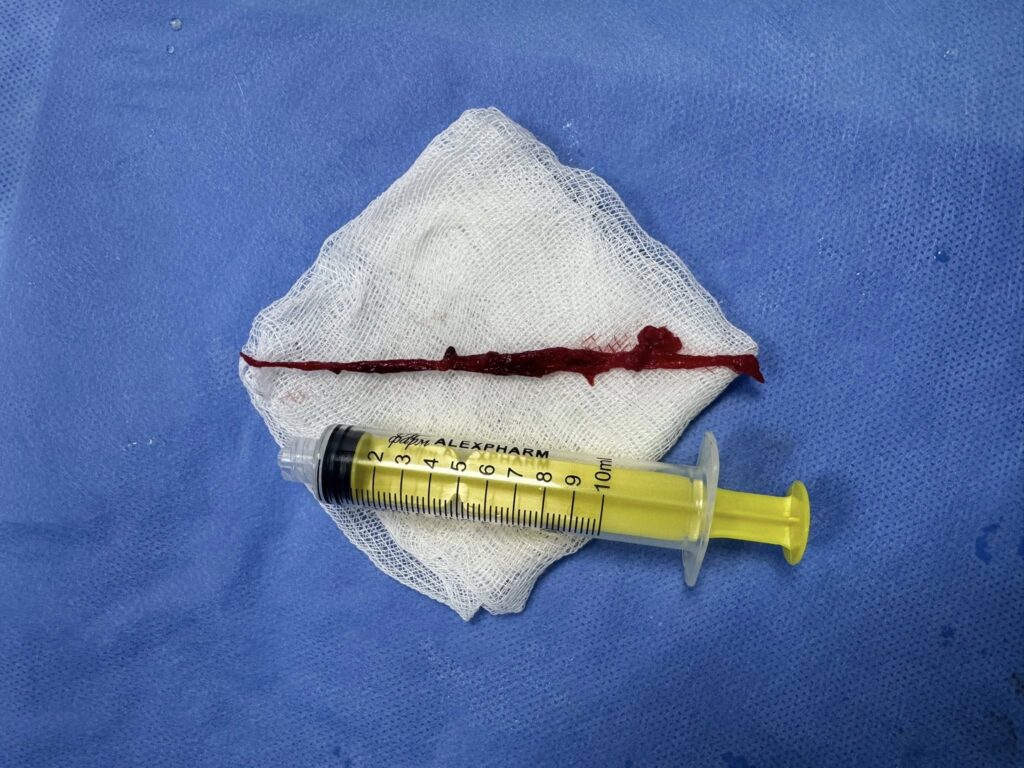

Під рентгенконтролем через судини катетером ми дісталися тромбів й видалили їх спеціальною системою аспірації.

Це перші успішні тромбаспірації при ТЕЛА, виконані у нашому об’єднанні.